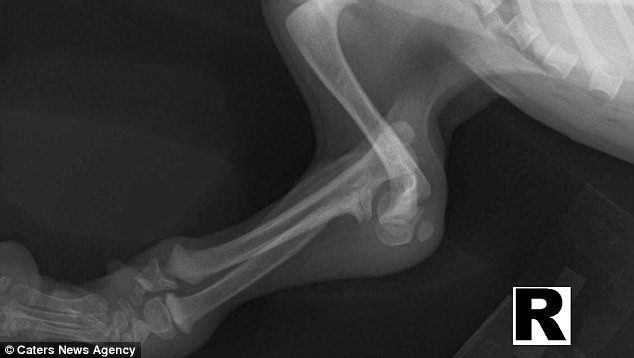

Рентгеновский снимок, на котором видно, как деформированы лапы собаки

Собаке была проведена операция, но она не помогла